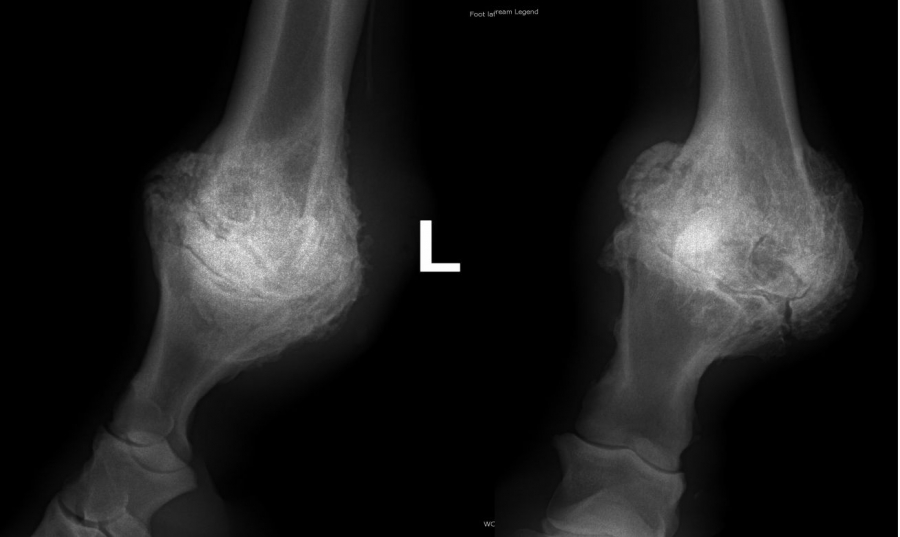

Těžká artróza ve spěnkovém kloubu